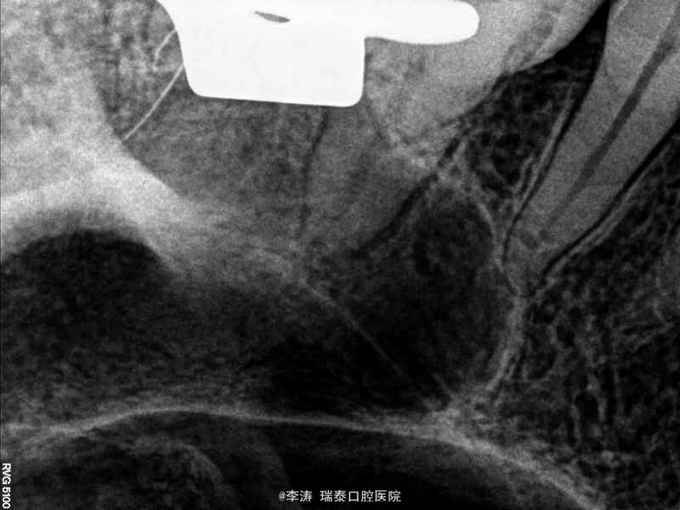

27牙伸长,松-,冷++,叩+-,近中邻面大面积龋坏,探及穿髓孔,x线片近中大面积龋坏近髓腔

27牙牙髓炎,行根管治疗 27磨短,测根长腭根11mm,近颊及远颊根15mm。置橡皮障,根管预备,根管消毒,根管充填。